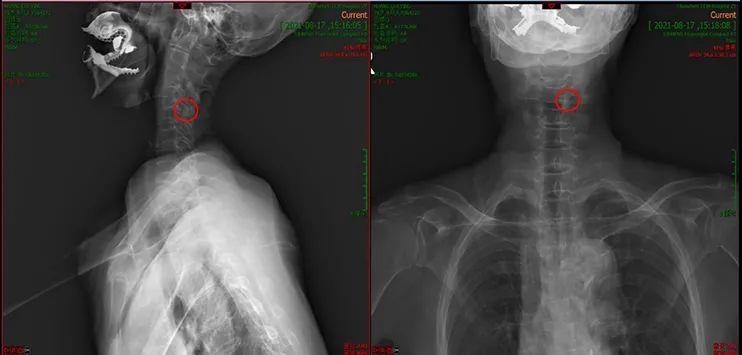

要准确区分真假痛风,实验室检查和影像学检查至关重要。关节液穿刺检查是最直接的方法。在显微镜下,真性痛风患者的关节液中会出现针状的尿酸盐结晶,而假性痛风患者则会出现片状或不规则状的焦磷酸钙结晶。此外,X线检查也能提供重要线索。假性痛风的X线表现主要为软骨和肌腱附着处的点状或线状钙化,而真性痛风则表现为关节面或骨端皮质的穿凿样、虫蚀样改变。